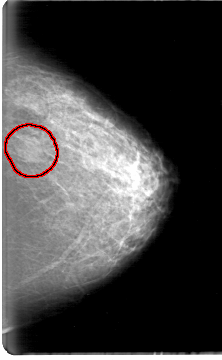

D_4058_1.LEFT_CC

LEFT_CC LINES 5386 PIXELS_PER_LINE 3316 BITS_PER_PIXEL 12 RESOLUTION 43.5 OVERLAY

FILE: D_4058_1.LEFT_CC.OVERLAY

TOTAL_ABNORMALITIES 1

ABNORMALITY 1

LESION_TYPE MASS SHAPE OVAL MARGINS OBSCURED

ASSESSMENT 0

SUBTLETY 3

PATHOLOGY BENIGN

TOTAL_OUTLINES 1

BOUNDARY